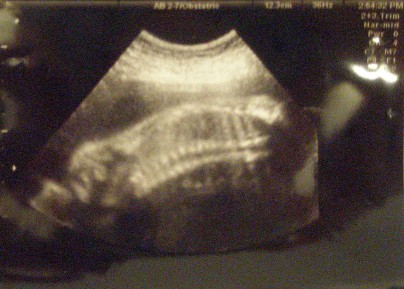

As for the baby, she couldn't be more perfect. My OB said she was measuring perfectly and her heartbeat is strong. Physically, this has been a rather uneventful pregnancy and I am very grateful.

I'll post pictures later but they make Ed-lie look like a lizard.

PICS of the lizard:

oh you have my lizard baby!!

my little is always sleeping face down like that... so cute

Seriously, her nose was so much cuter the last time. Im going to say she wasn't as cooperative this time and maybe when I go for my GTT next week, I can sneak in another sono and figure out if I need to start saving for college or rhinoplasty.